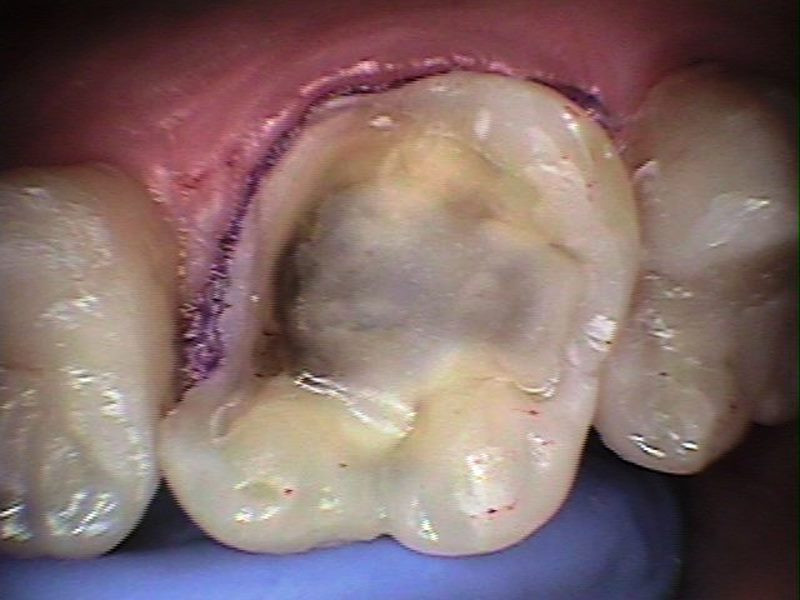

Molar preparado para toma de impresión